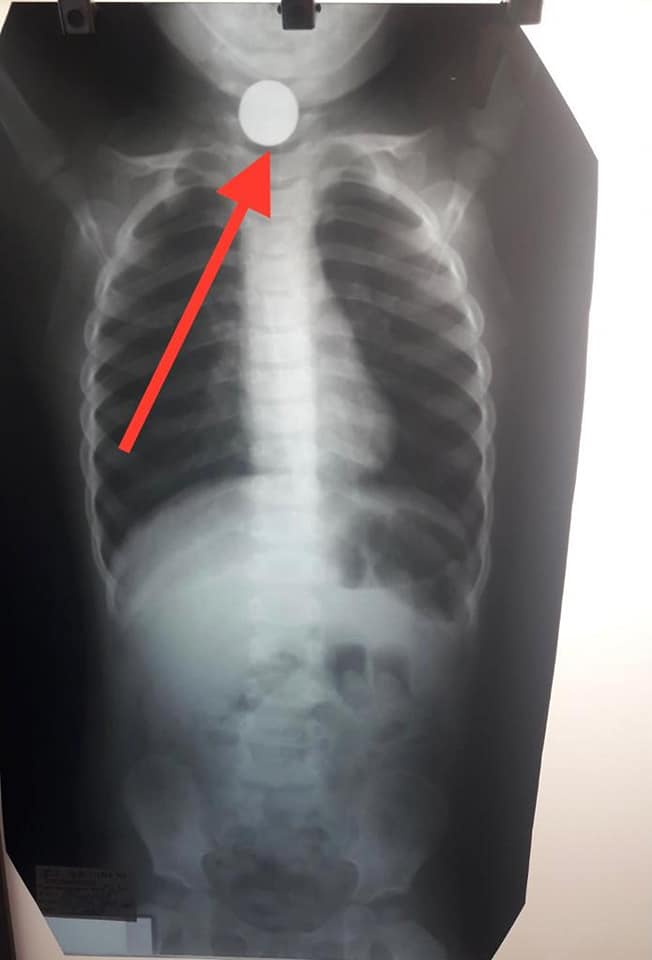

В Харьковскую областную детскую клиническую больницу №1 в один день поступили двое детей, которые проглотили монеты номиналом 1 гривна и 50 копеек. Об этом сообщили на странице медучреждения в Facebook.

Оба случая произошли 11 ноября.

Монеты извлекла заведующая отделением торако-абдоминальной хирургии врач-эндоскопист Наталья Романова. Теперь они станут экспонатами Музея извлеченных предметов.

"Закон парных случаев, как говорят в медицине. Разный возраст, но интерес к деньгам уже имеют", — написали сотрудники ХОДКБ №1.